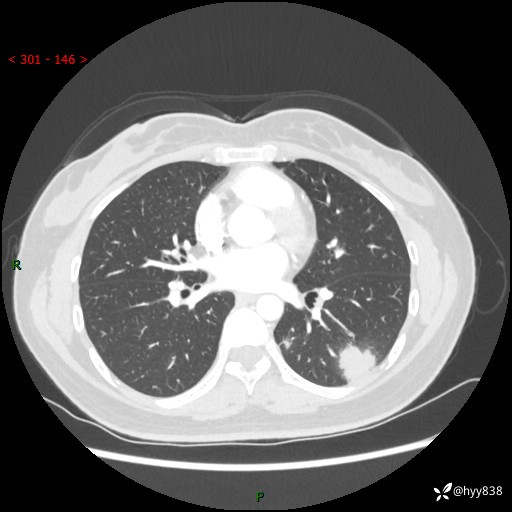

【患者信息】:36岁/女

【主诉】:左侧下胸部阵发性疼痛2周,乏力1周

【现病史及既往史】:患者自诉2周前饮酒后出现左侧下胸部阵发性疼痛,不随呼吸改变,无咳嗽咳痰、头晕头痛、咳血、呼吸困难等不适,于当地第一人民医院查胸部CT提示肺部感染,随后前往我院门诊给予抗感染(左氧氟沙星)治疗1周,自诉胸痛较前好转,感乏力、头晕,偶尔干咳,无咳痰,无发热、畏寒、胸闷、咯血、四肢酸痛、腹泻、腹痛等不适,门诊复查胸部CT提示:左肺下叶感染,病灶较前增加增大,遂以“肺部感染”收入我科。 起病以来,患者精神、饮食、睡眠可,大小便正常,体力体重无明显变化。

【检查】:胸部CT增强(外院平扫)